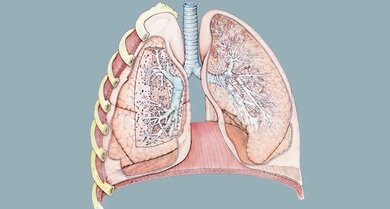

Die Lungen sitzen auf dem Zwerchfell, in der Mitte dazwischen liegt das Herz (hier nicht dargestellt; schematisch)

Der größte Atemmuskel, das Zwerchfell, bewegt bis zu zwei Drittel der Atemluft. Beim Einatmen zieht es sich zusammen, die Lungen dehnen sich nach unten aus. Die kleinen (inneren und äußeren) Atemmuskeln zwischen Rippen unterstützen die Atembewegungen. Als Atemhilfsmuskeln wirken vor allem größere Brustmuskeln, Muskeln des Schultergürtels und am Hals.